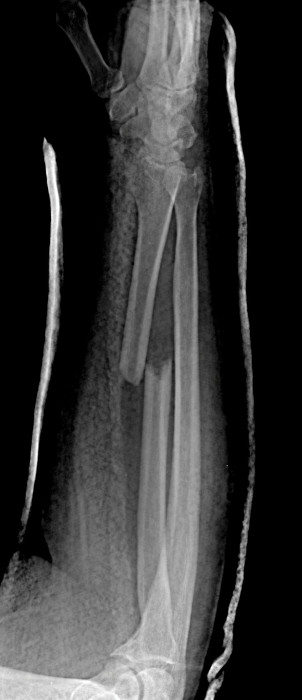

Radial Shaft Fracture